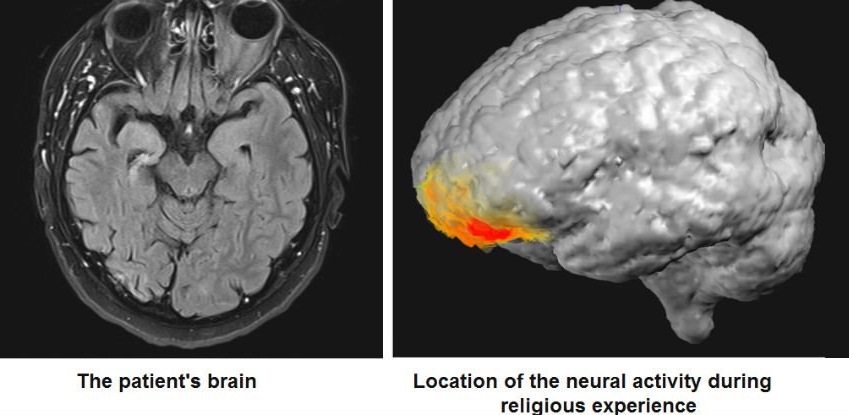

Pacientul trecea printr-un tratament pentru epilepsie, care l-a făcut să „vadă” şi să converseze cu figura lui Dumnezeu. În acest moment ”divin”, pacientul era conectat la un scaner cerebral de EEG (electroencefalogramă).

După cum relatează Neuroskeptic, scanările cerebrale dezvăluie o activare în banda gamma de jos (30-40 Hz), în cortexul prefrontal stâng. În momentul exact al experienţei supranaturale s-a activat partea exact opusă a creierului unde proveneau crizele lui epileptice.